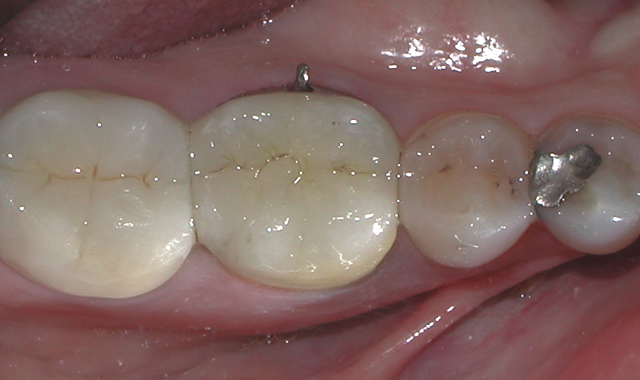

One week later, the PFM crown for tooth #30 was delivered to my office for insertion. The provisional was removed and the PFM placed to check, adjusting the fit and occlusion as needed. Finally, the patient’s new PFM crown for #30 was definitively cemented using glass ionomer luting cement (Ketac™ Cem, 3M ESPE) (Figs. 14-15).

Fig. 14 Fig. 15